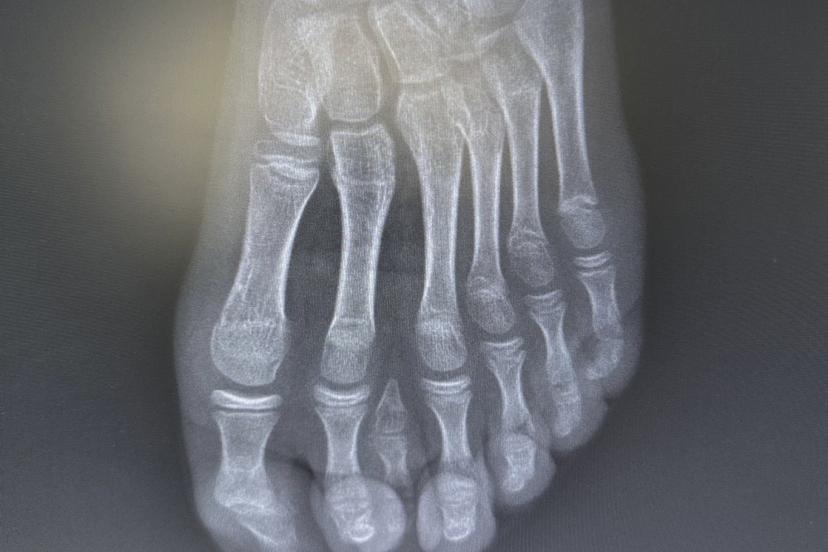

Batman Eğitim ve Araştırma Hastanesinde, 8 yaşındaki E.H. isimli hastada nadir görülen doğumsal bir ayak anomalisi başarıyla tedavi edildi.

Yetkililer, el ve ayaklarda fazla (polidaktili) ya da eksik parmak vakalarına zaman zaman rastlandığını ancak 7 parmaklı ayak olgularının oldukça nadir görüldüğünü belirtti.

Genel yaklaşımda bu tür vakalarda cerrahi planlamanın ayağın beş parmaklı anatomik yapısına uygun şekilde yapıldığı ifade edildi. Ancak hastanın yapılan detaylı klinik ve radyolojik değerlendirmelerinde altı parmağın; falanks (parmak kemikleri), metatars (tarak kemikleri) ve diğer ayak kemikleri ile uyumlu ve düzgün şekilde geliştiği tespit edildi.

Uzmanlar, mevcut altı parmağa müdahale edilmesinin ayak biyomekaniğini ve dengesini olumsuz etkileyebileceğini değerlendirdi.

Bu doğrultuda cerrahi planlama yeniden yapılarak, fonksiyonel açıdan yetersiz ve estetik olarak problem oluşturan tek parmağın çıkarılmasına karar verildi. Operasyon sırasında diğer parmaklara ait damar ve sinir yapıları titizlikle korunurken, mikrocerrahi teknikler kullanılarak işlem sorunsuz şekilde tamamlandı.